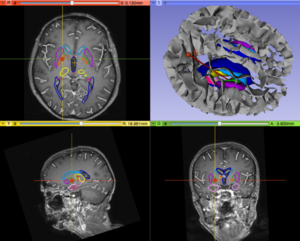

Pydbs.png

• Upgrade of the PyDBS modules for Parkinson Surgery to Slicer4.4